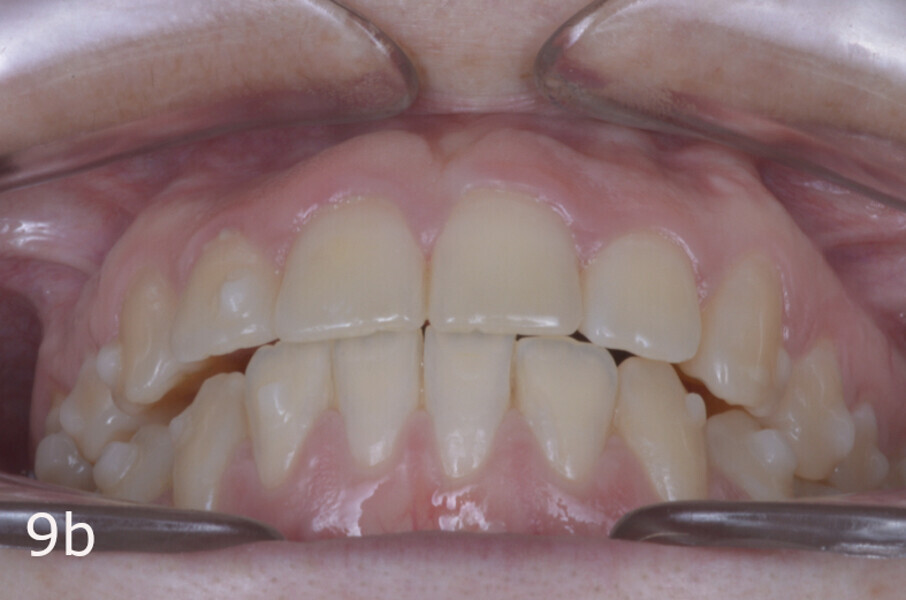

The treatment objectives included closing the anterior open bite, achieving a bilateral Angle Class I relationship and a proper overjet and overbite, correcting the midline discrepancies, and achieving a profile harmonisation. The treatment plan consisted of orthodontic camouflage treatment with asymmetric distalisation in three of the four quadrants using Invisalign aligners (Align Technology) and third molar extraction. The Invisalign Comprehensive package was chosen, and 63 pairs of aligners were used (Figs. 7–10). Each aligner was worn for 20 hours a day for one week each. The use of Class III elastics on both sides was indicated. Afterwards, ten refinement aligners were needed to improve the interdigitation on the right side (Figs. 11 & 12).

Although Class III elastics tend to extrude the maxillary molars and generate clockwise mandibular rotation, aligners allow us to prevent these complications, since we have better control over tooth movement, enabling us to counteract unwanted dental movements. In this case, an intrusion of the posterior teeth was planned, which would generate anticlockwise rotation of the mandible in an anticlockwise direction. This vertical control led to the closure of the anterior open bite and the reduction of the lower facial height, thereby improving the facial profile.

The total treatment time was 15 months. An Angle Class I relationship was established along with adequate anterior and canine guidance, establishing a functional occlusion. This not only ensures optimal masticatory function but also protects the teeth and the temporomandibular joint from excessive force. Maxillary and mandibular fixed retention were installed at the end of the treatment (Figs. 13–19).